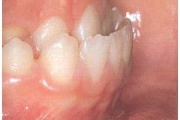

Ravijärgne seis. Jäävhammas on täielikult lõikunud.

Esimese jäävmolaari ektoopiline lõikumine